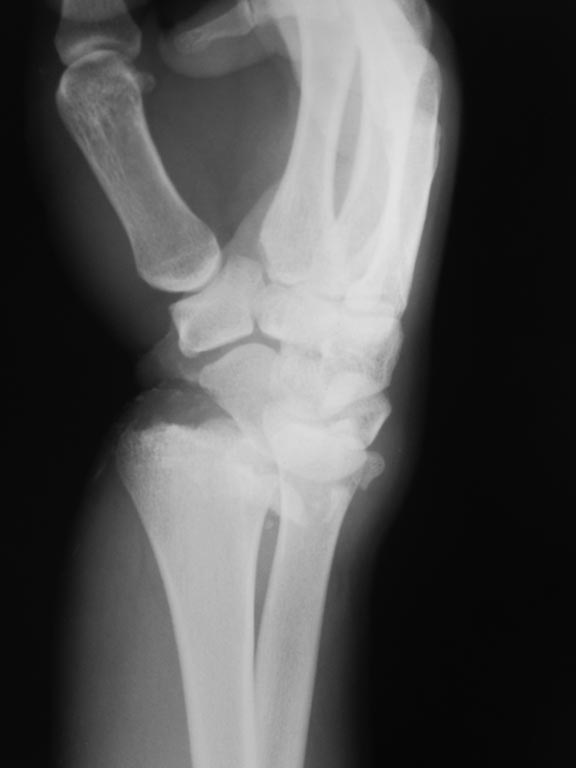

Рентгенограммы:

Это классический переломо-вывих в лучезапястном суставе, выделенный АО в отдельную подгруппы - 23-В2.3. В свежем случае здесь показано закрытое вправление и наружная фиксация повязками или аппаратом, в качестве окончательного метода для предотвращения нестабильности сустава рекомендуется восстановление капсулы сустава, в первую очередь тыльной - т.е. репозиция и фиксация всех этих мелких фрагментов, послеоперационная иммобилизация аппаратом внешней фиксации